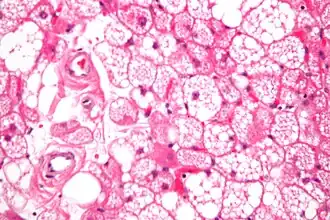

Los tumores se parecen histológicamente a la grasa parda. Se reconocen cuatro tipos histológicos, pero uno es el más frecuente (típico). Se observa un entorno rico en vascularización .

- Tipo lobulillar: grados variables de diferenciación de células uniformes, redondas a ovaladas con células eosinófilicas granulares con bordes prominentes, que se alternan groseramente con adipocitos multivacuolados. Por lo general, hay pequeños núcleos ubicados en el centro sin pleomorfismo. Las células tienen grandes gotas de lípidos citoplasmáticos grandes diseminados por todas partes.[1][2]

Hibernoma (aumento intermedio).